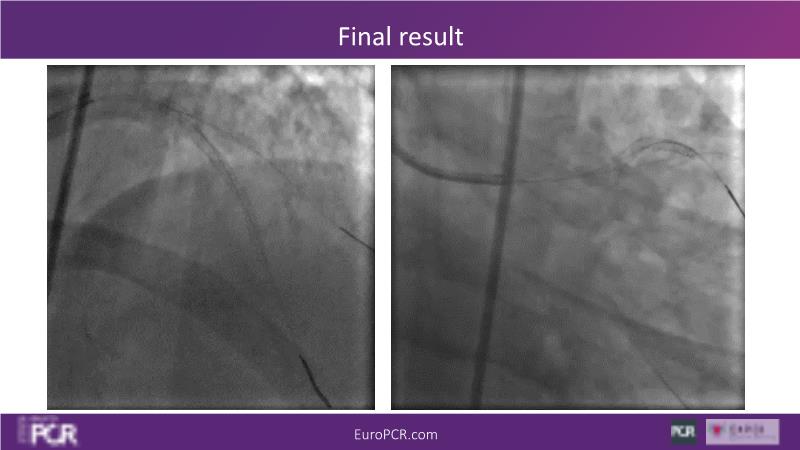

Watch this session on PCI in diabetic patients to learn about a groundbreaking technology addressing the complexities of this critical subgroup. Discover the next-generation DES and DCB stent platform and the innovative Envisolution technology behind it. Understand how it works, its advantages in managing complex cases, and what sets it apart from other technologies. Gain insights into the future of polymer-free DES + DCB stent technology and its potential impact on patient care.